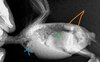

Неплохо выполнен рентген. Напишите адрес и наименование клиники, и как врача зовут.

По снимку. Ничего хорошего.

1.Оранжевым указала остро увеличенные почки, скорее всего- неоплазия.

2.Зеленым- зона где должна быть нормально печень, а сейчас там муть одна, матовое стекло, возможно- под ней сидят злые семенники . Возможен цирроз на фоне онкопроцесса, или кровоизлияние .

3.Голубым- то ли неоплазия зоба, то ли стороннее включение по типу комка ниток/бумаги.

С учетом 1 и 2- скорее неоплазия.

Итог- неутешительный. Велика вероятность злокачественного новообразования почек или семенников, с MTS в печень и слизистые зоба.

вот поиграла со снимком